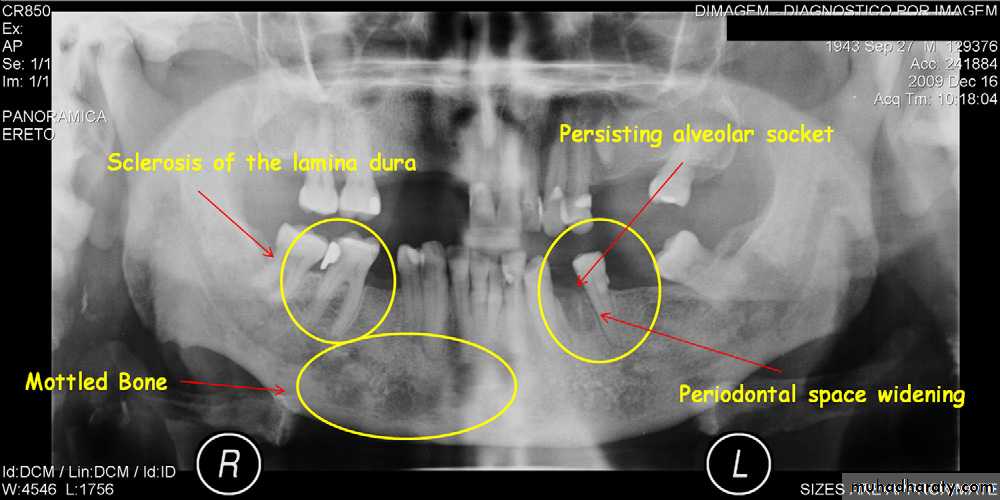

Osteoradionecrosis of the maxilla. (A) before radiotherapy and (B) within 6 months of receiving the radiation. Note the combination of bone sclerosis, bone destruction around the teeth and alveolar crest and widening of the periodontal membrane space.

B

A

• Presence of sequestra . • Increase in bone sclerosis. • Widening of PDL space • Thicknening of lamina dura.

( A and B ) of the same patient taken 7 years apart reveal thickening of the lamina dura around the teeth.